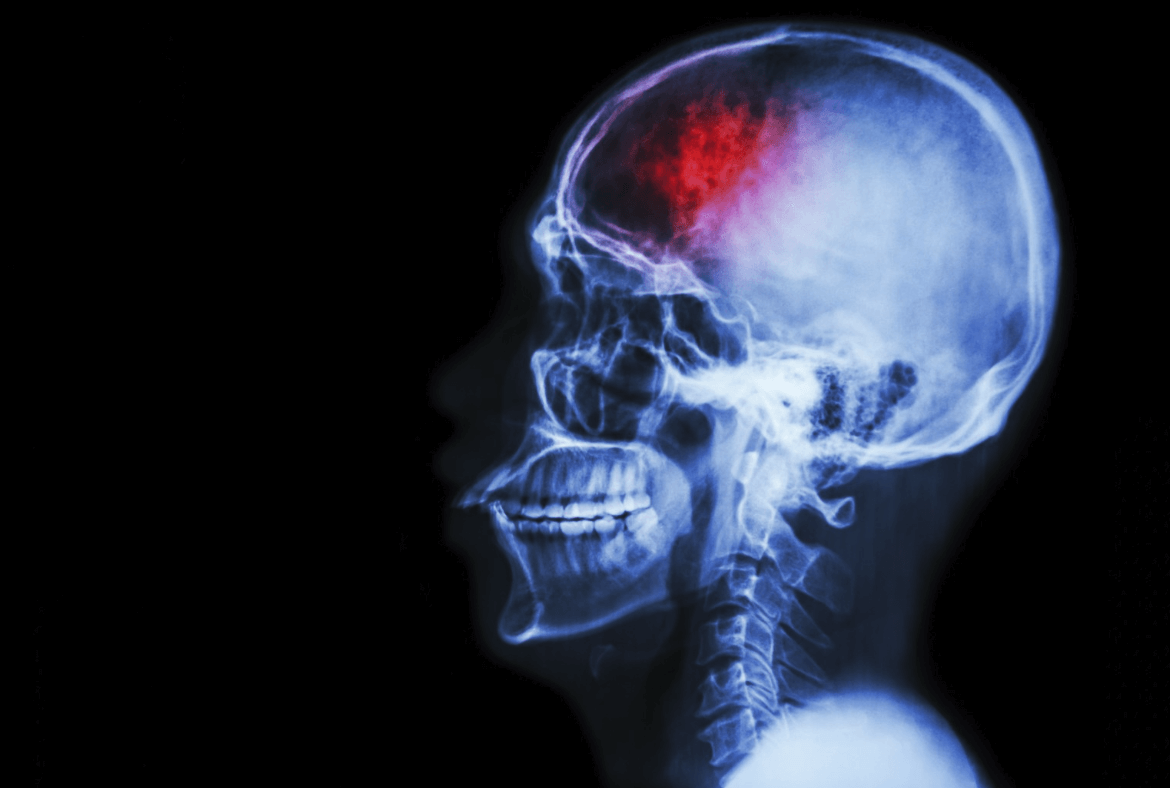

A sinus headache is categorised as a headache that’s bilateral in nature with symptoms felt on both sides of the sinus, face and nose. Sinusitis, whether allergic, nonallergic or fungal, can cause changes in the pressure in the sinuses.

However, the sinus infection itself is often not the cause of the headache. Indeed, sinus infections will often trigger neck pain, which in turn causes the referred pain around the head and is the actual cause of the headache. In a 2019 study, researchers reported 84% of sinus headache sufferers reported neck pain associated with headaches.